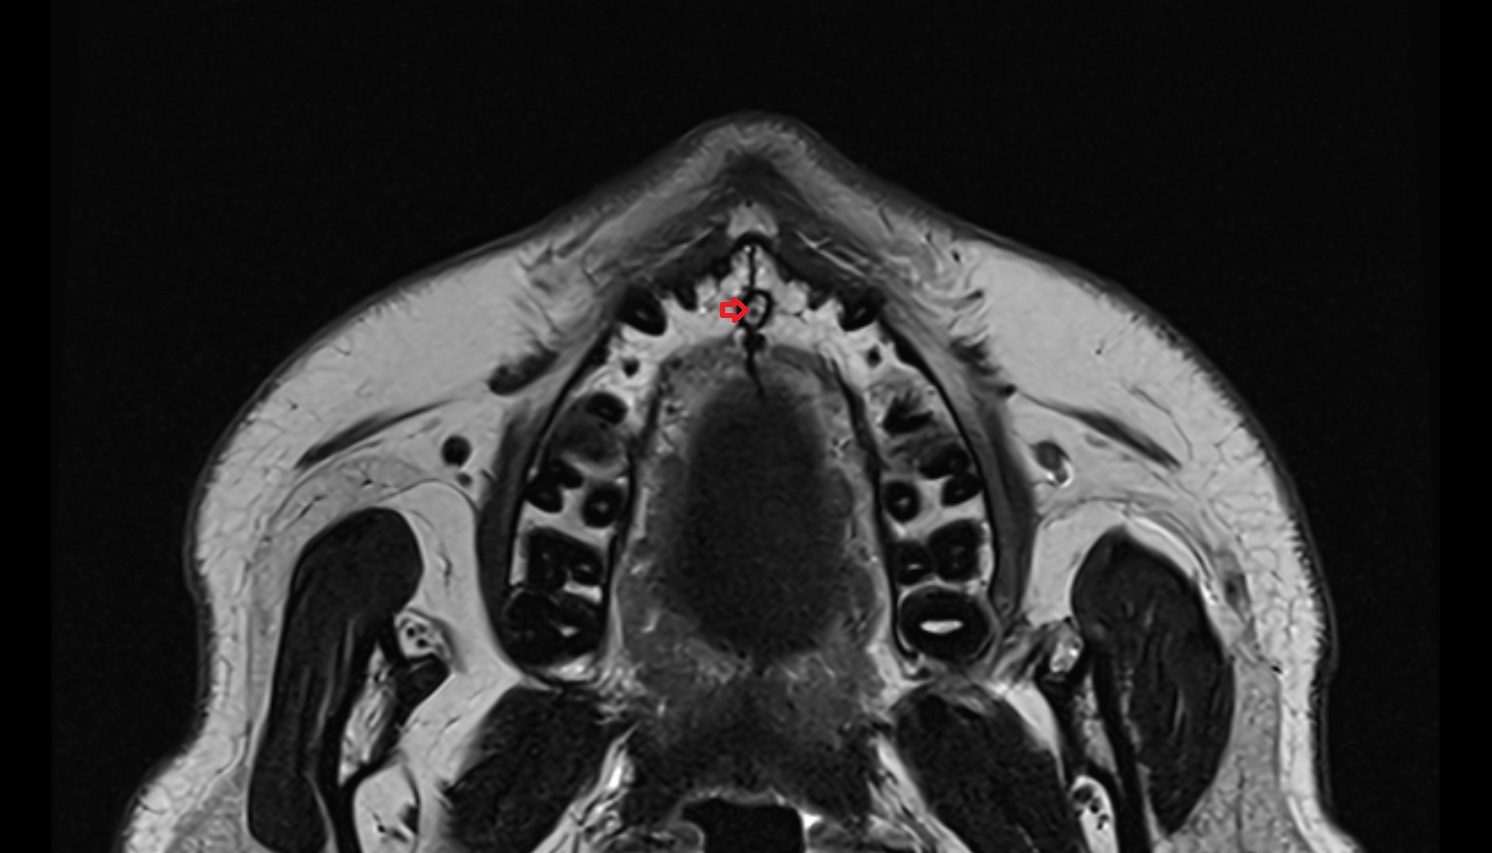

- Temporomandibular joint

- Mandibular condyle

- Mandibular fossa

- Superior head of lateral pterygoid muscle

- Inferior head of lateral pterygoid muscle

- Lateral pterygoid muscle

- Masseter muscle

- Medial pterygoid muscle

- Temporalis muscle